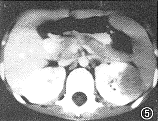

图5 与图4同一病例。增强CT显示左肾实质内单发结节影,密度均匀

图6 与图4同一病例。B超显示肾实质内孤立的中等强度回声结节

11例白血病肾浸润患儿中,9例为双肾浸润,其中双肾弥漫浸润4例,双肾多发结节浸润5例,9例中ALL 8例,ANLL 1例。CT平扫见弥漫浸润为两肾轮廓增大,肾包膜完整光滑,肾实质明显增厚,肾实质密度无异常,肾窦形态基本正常,增强后肾盂、肾盏显影轻度延迟。B超显示肾影增大、肾实质增厚的同时还显示回声均匀增强。 多发结节浸润的平扫CT见肾实质内多发的略高密度结节影,结节间可见线状低密度影将其分开(图1),结节突起使肾表面呈轻度分叶状。增强后肾实质内结节呈轻微强化,较平扫增长18 HU,密度均匀,结节内无低密度坏死区或出血,结节间见强化后受结节挤压变形的肾实质与集合系统,呈高密度分支状影(图2),肾实质强化程度较正常减低,在结节间自肾被膜下延伸至肾窦,肾盏变形拉长,肾盂显影明显延迟。B超显示肾实质回声增强,内见多发大小不等的结节(图3),中等强度回声,肾结构不清。化疗后复查,CT平扫显示双肾大小、形态基本恢复正常。本组2例呈单发结节浸润,均为ANLL。平扫CT见肾实质局限增厚,表面隆起,密度较正常肾实质略高,境界模糊(图4),增强后见肾实质内单发结节状影轻微强化,较平扫增长22HU,结节与正常肾实质间界限清楚(图5),肾被膜完整。B超显示肾实质内孤立中等强度回声结节(图6),肾结构受挤压变形。化疗后复查B超显示肾形态基本恢复正常。 本组化疗后5例复查CT与B超,显示肾轮廓明显缩小,肾实质厚度、密度或回声接近正常。11例患儿肝、脾均有不同程度增大。8例ALL患儿CT或B超检查同时显示胸腺浸润1例;肺及胸膜浸润4例;肾上腺浸润2例;腹膜后淋巴结浸润1例。3例ANLL患儿除肝、脾增大外CT或B超检查未显示其他脏器浸润。